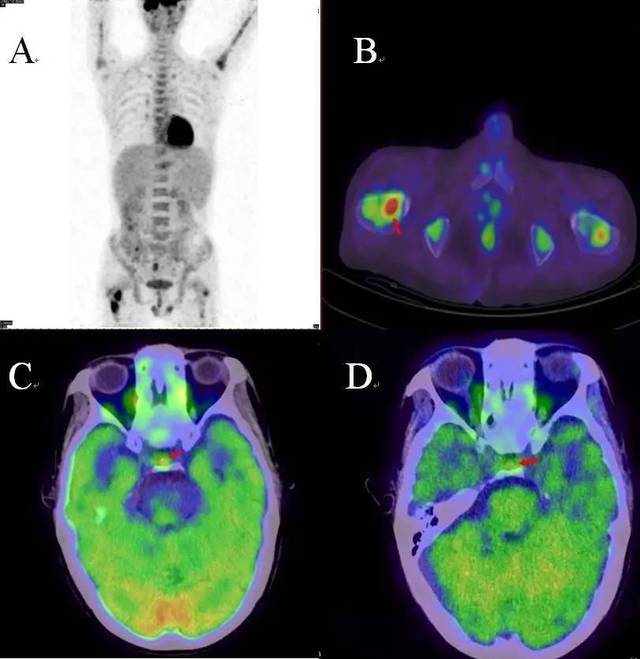

PET\/CT-MR 异机融合

【病例】PET\/CT,头痛的脑病变!

规培朋友看过来--核医学病例及解析(183号)

规培朋友看过来--核医学病例及解析(183号)